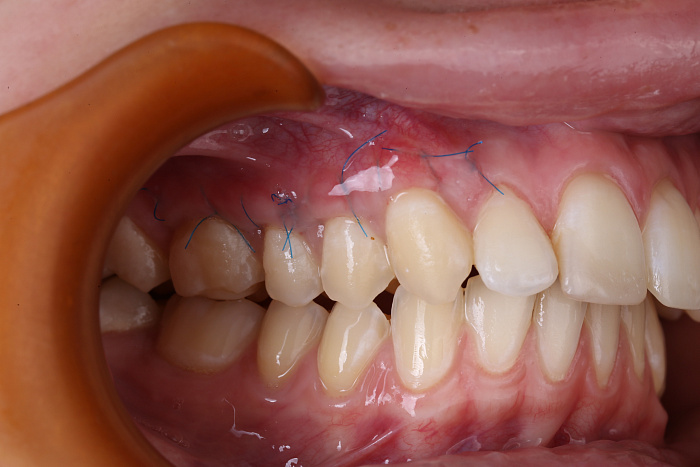

Лоскутная пластика — классический метод, при котором берётся участок слизистой с неба или другого участка десны и пересаживается в зону рецессии. Донорская ткань укрепляется швами, приживается в течение 1–2 недель. Также может применяться десневой трансплантат, в том числе СДТ (свободный десневой трансплантат), ДСДТ (десне-надкостничный трансплантат) или ССТ (соединительнотканный трансплантат).

Используется микрохирургический инструментарий, лазерное и ультразвуковое оборудование для щадящей подготовки тканей. Применяются сертифицированные биоматериалы.

После вмешательства пациенту рекомендуется соблюдать мягкую диету, исключить механическое и температурное раздражение зоны операции, отказаться от физических нагрузок. Швы снимаются через 7–10 дней. Эстетический эффект заметен уже через 2–3 недели.

Результаты работ